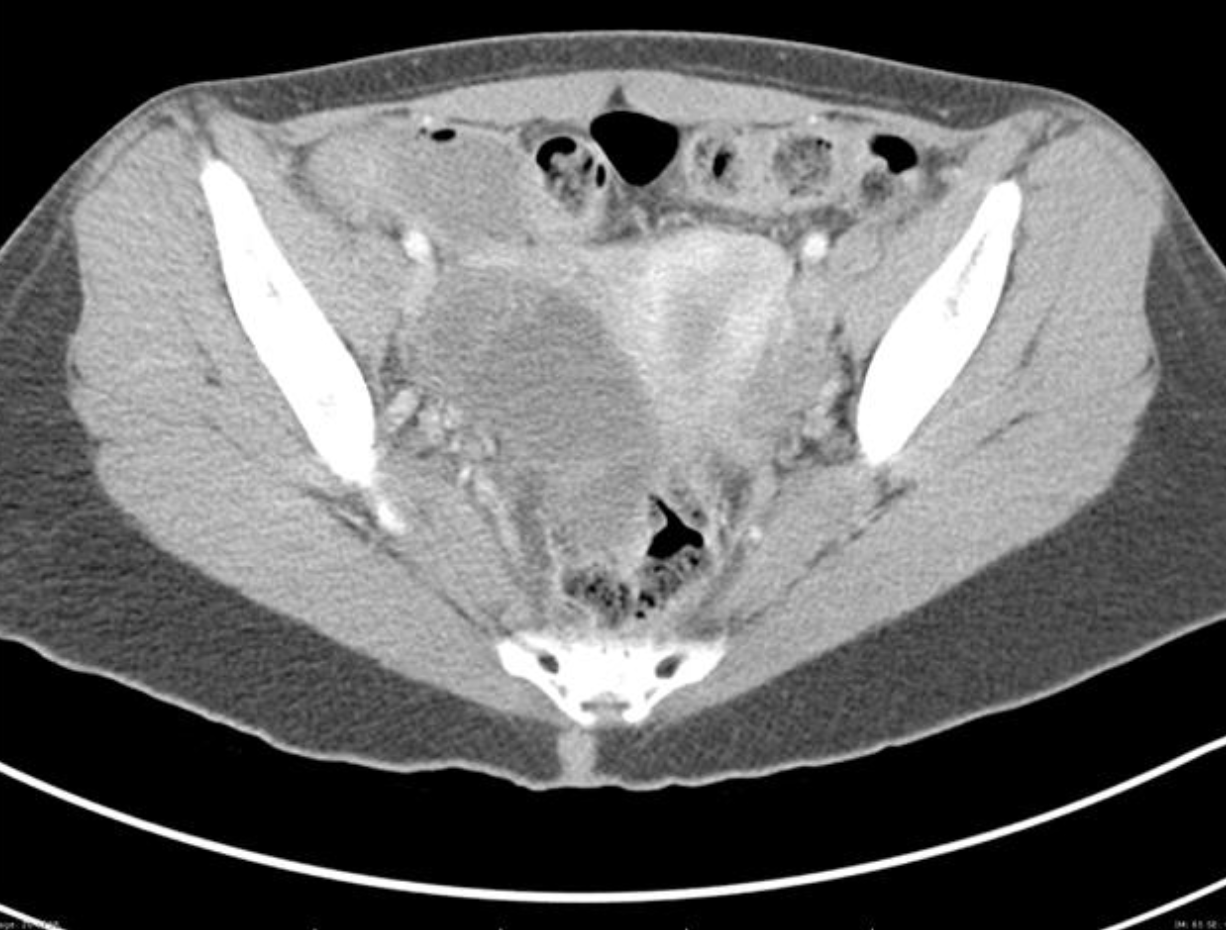

A CT of the abdomen/pelvis may also demonstrate TOA. It is not the preferred method of diagnosis due to radiation exposure and its inability to assess for other ovarian pathology (torsion). CT is frequently ordered in patients to evaluate for appendicitis or other suspected etiology and the scan may reveal a TOA instead. The CT scan above reveals a complex ovarian mass consistent with TOA.

Figure: Complex mass into the anatomical space consistent with TOA. Radiopaedia. Image used under the Creative Commons Attribution-Share Alike 3.0 Unported license.

Figure: Right adnexa showed a complex cystic mass consistent with TOA. Radiopaedia. Image used under the Creative Commons Attribution-Share Alike 3.0 Unported license.

A pelvic ultrasound is warranted if a TOA is suspected or the diagnosis is unclear. It is particularly useful to rule out other diseases that may present with pelvic pain such as a ruptured ovarian cyst (free fluid in the pouch of Douglas) or ovarian torsion (absence of blood flow to one ovary on pelvic ultrasound with Doppler). The absence of radiographic findings does not rule out PID.